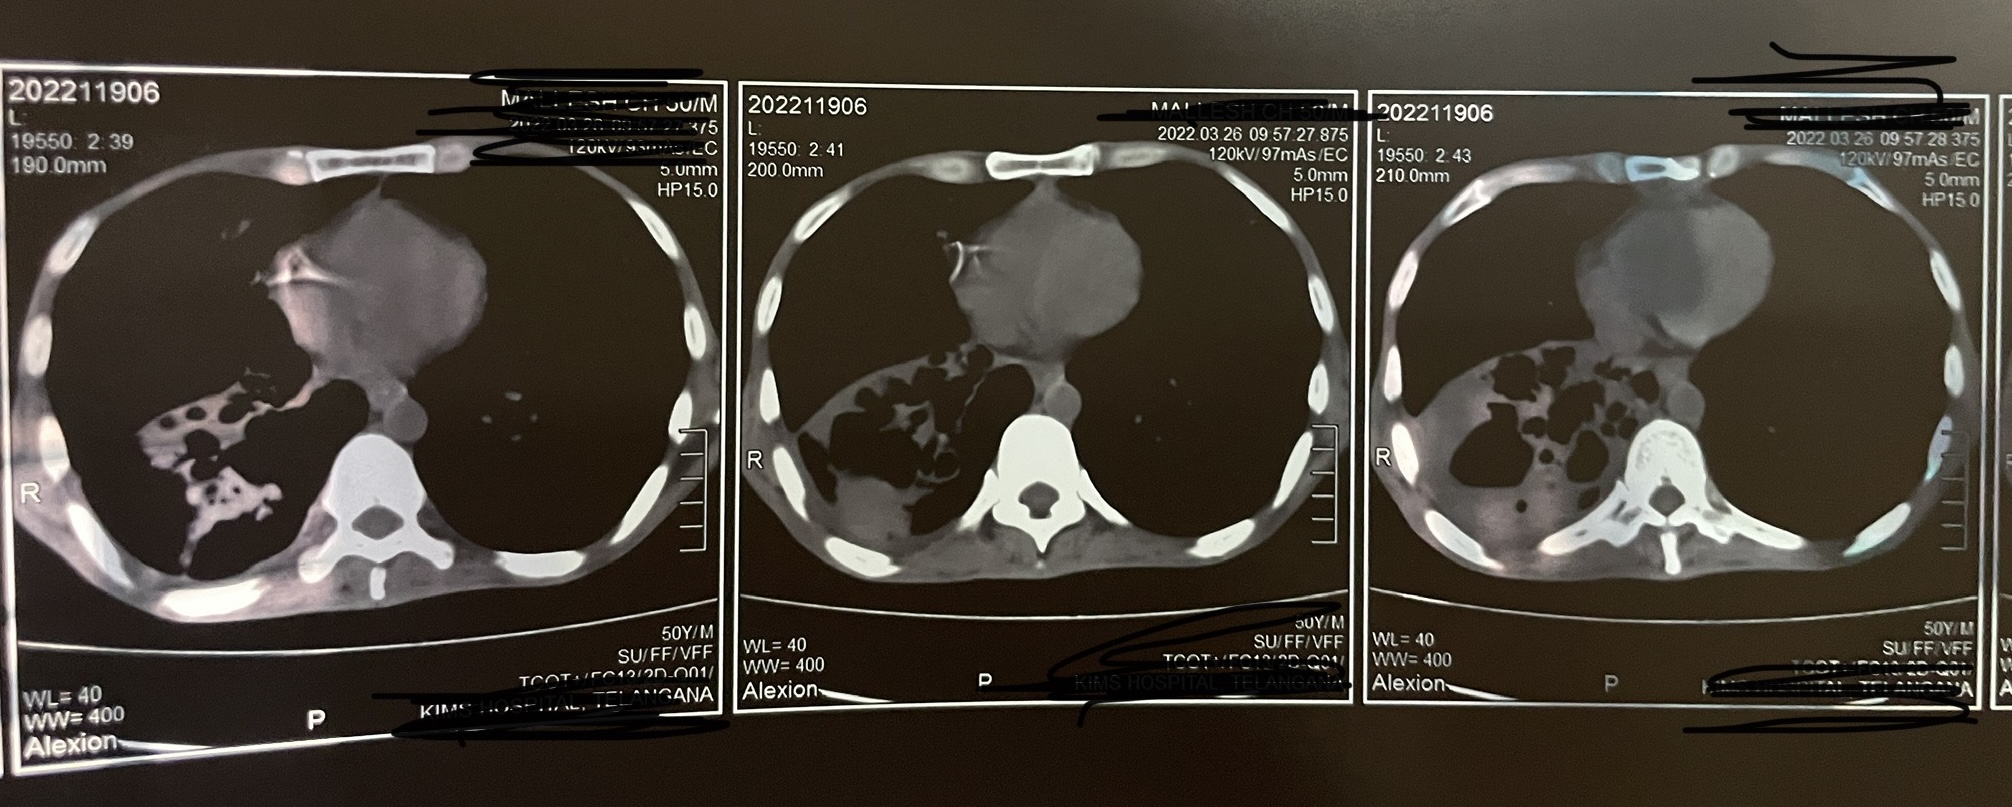

HRCT:

Clinical images: